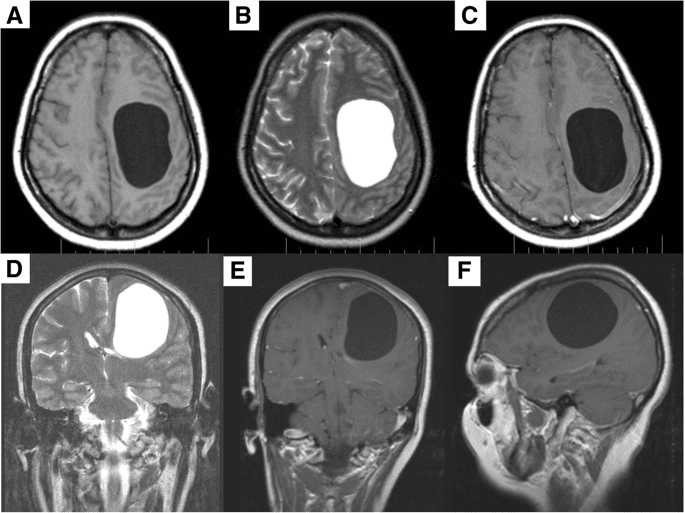

سيُجري طبيبك فحصًا بالتصوير المقطعي المحوسب (CT) أو تصويرًا بالرنين المغناطيسي (MRI) لتشخيص الكيس العنكبوتي. تُظهر هذه الاختبارات أيضًا موقع الكيس وحجمه، ما يساعد طبيبك على معرفة كيفية علاجه.

نظرًا لأن معظم الأكياس العنكبوتية لا تسبب أعراضًا ، فإنها تُكتشف عن طريق الصدفة أيضًا عندما يخضع الشخص لفحص الدماغ لسبب آخر ( مثلا بعد حادث سيارة أو سكتة دماغية).